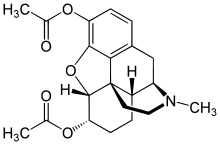

- Esters of morphine opiates: slightly chemically altered but more natural than the semi-synthetics, as most are morphine prodrugs, diacetylmorphine (morphine diacetate; heroin), nicomorphine (morphine dinicotinate), dipropanoylmorphine (morphine dipropionate), desomorphine, acetylpropionylmorphine, dibenzoylmorphine, diacetyldihydromorphine;[261][262]